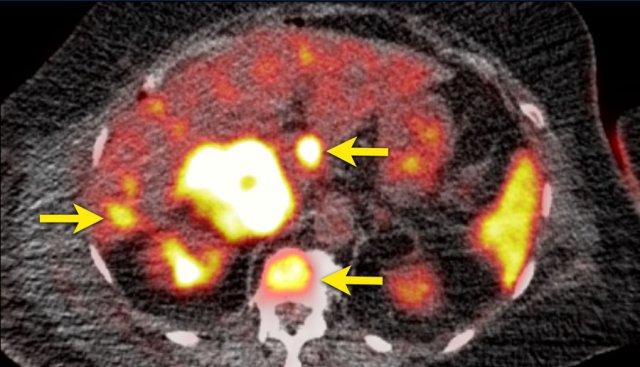

Hình ảnh thể hiện cửa sổ trung thất và cửa sổ xương của một bệnh nhân có khối u tuyến thượng thận phải kích thước lớn, ngấm thuốc không đồng nhất.

Khối u này đã được xác nhận là ung thư biểu mô vỏ thượng thận.

Có một tổn thương gan mờ nhạt, bờ không rõ ở phân thùy 6 và các thay đổi xơ cứng không đặc hiệu ở thân đốt sống T12.

Tiếp tục xem hình ảnh PET…

PET-CT thực hiện để phân giai đoạn toàn diện cho thấy sự hấp thu mạnh tại khối u tuyến thượng thận, gợi ý bản chất ác tính của khối u.

Ngoài ra còn ghi nhận sự hấp thu mạnh tại hai ổ di căn gan và một ổ di căn xương ở T12.